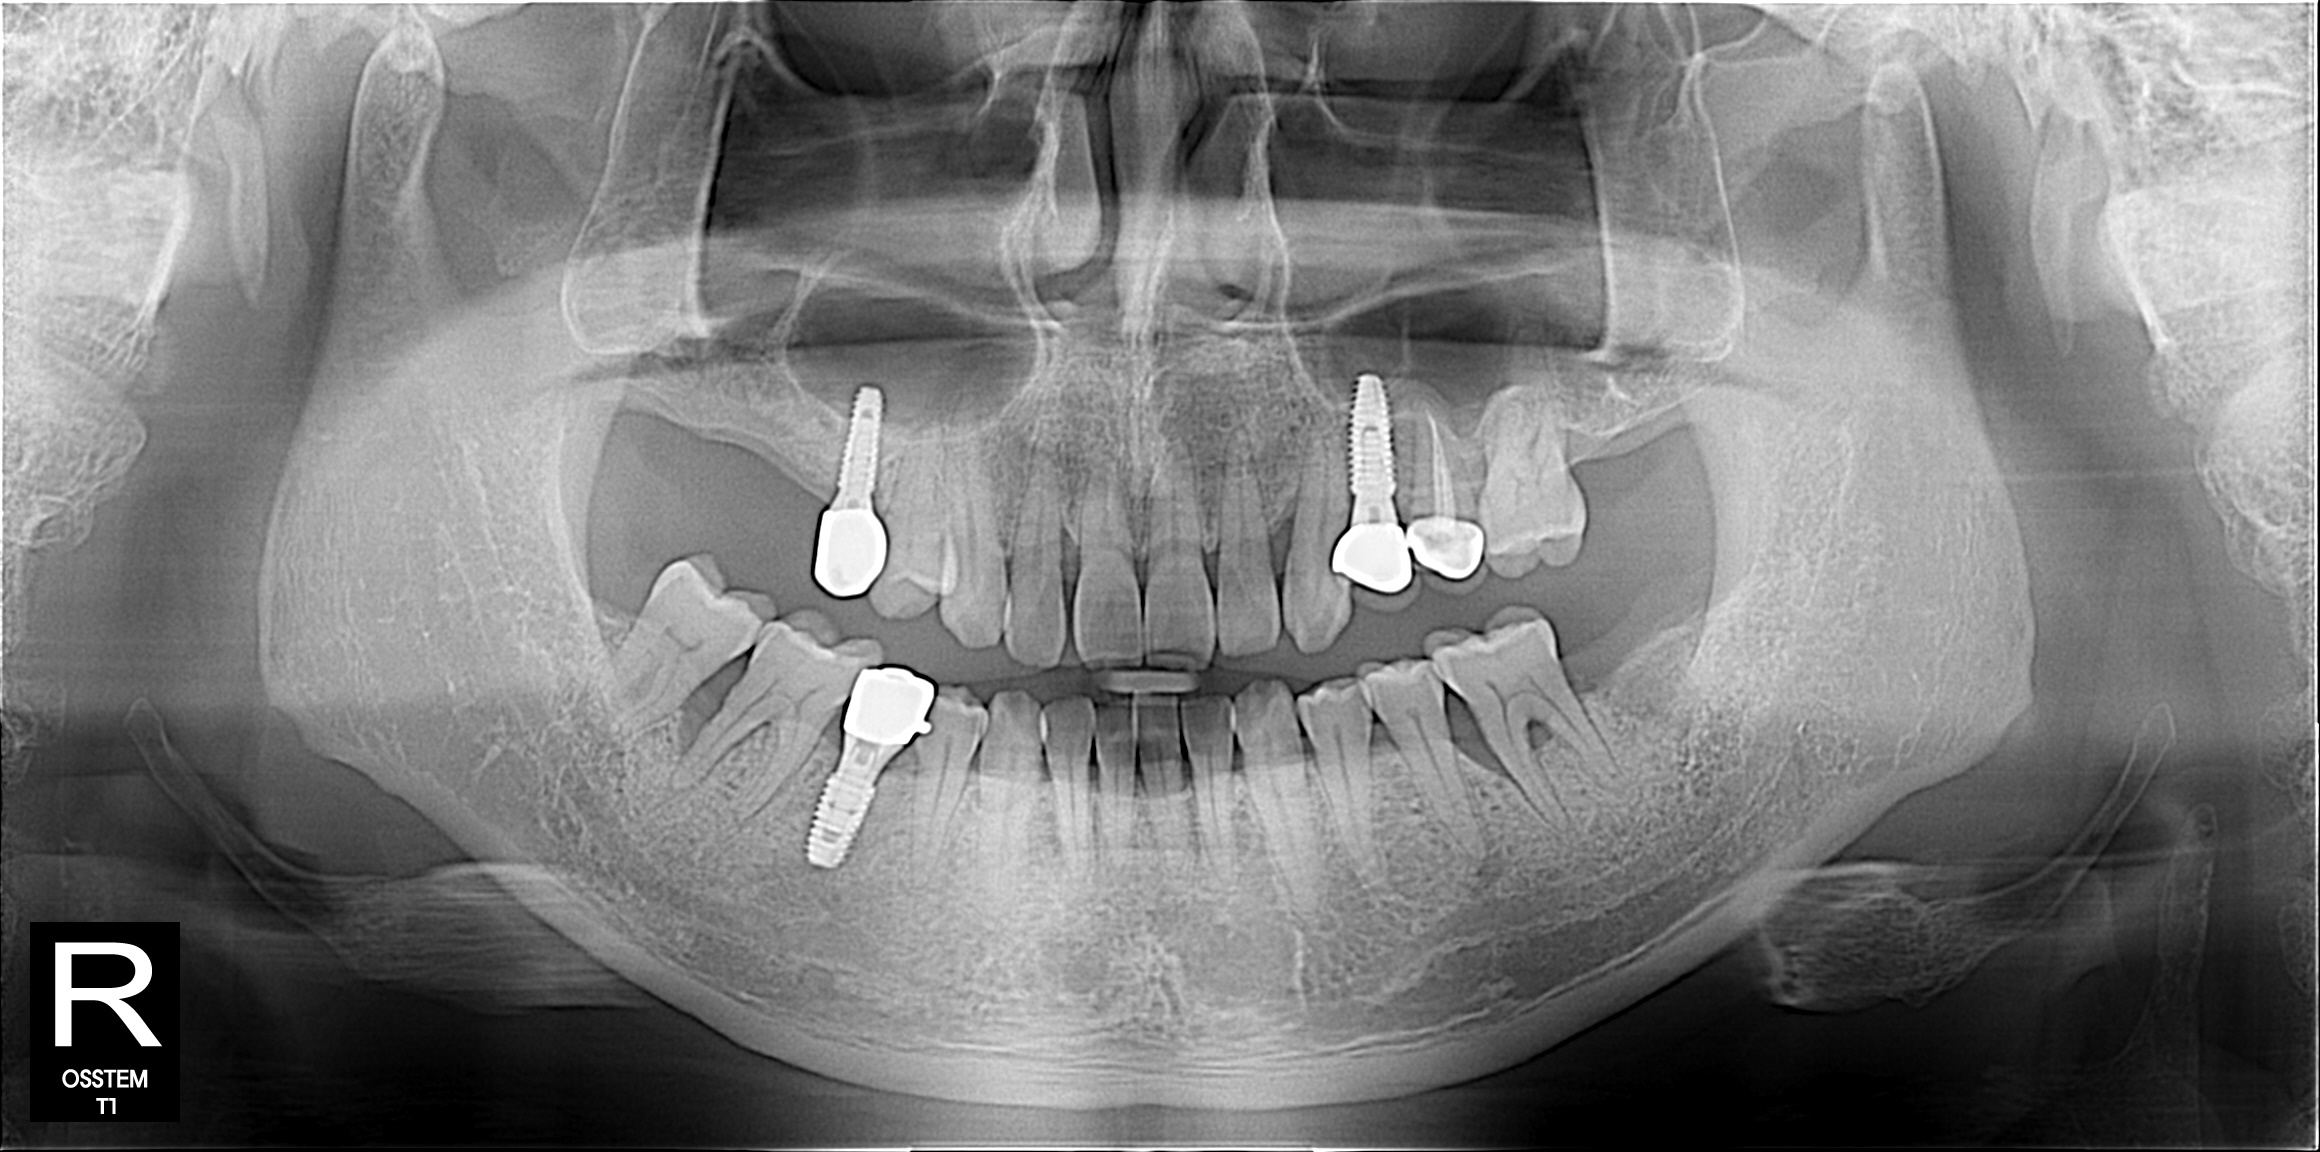

임플란트

BEFORE & AFTER